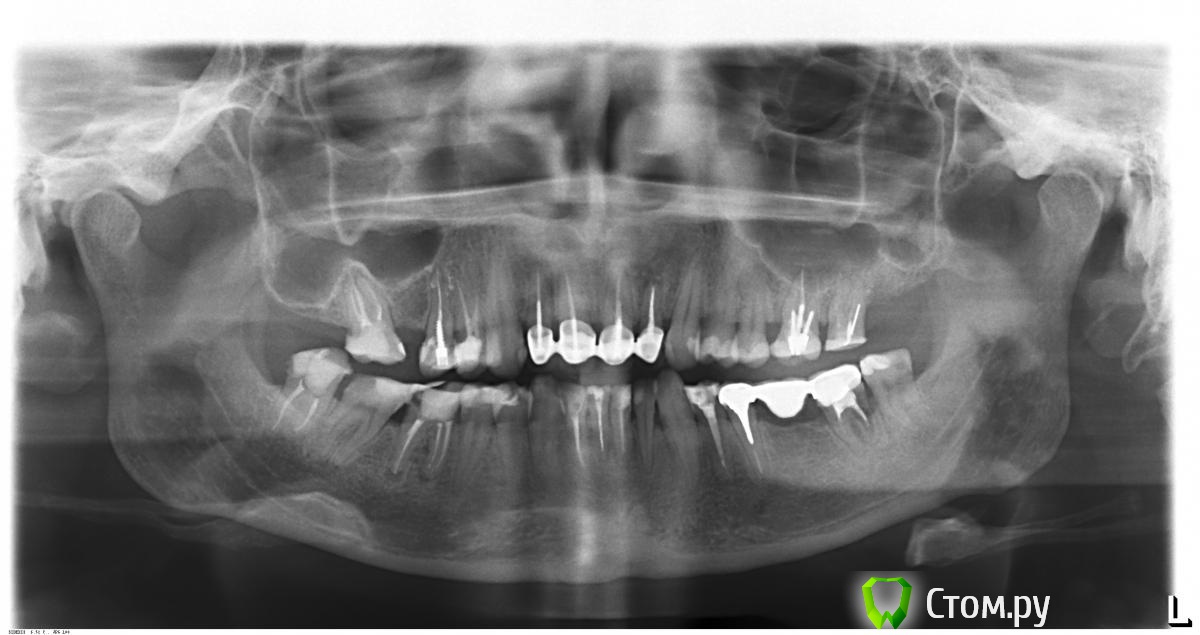

Юлия09 Опубликовано 3 декабря, 2013 Поделиться Опубликовано 3 декабря, 2013 Добрый вечер! Какой план лечения к этому ОПТГ? И еще выпала пломба из 26, хотелось бы до НГ поставить коронки, но говорят не хватает высоты? Если бы кто то в Москве мог помочь:-) И самый страшный вопрос во время лечения мне делали вкладки e-max 4 и 5 справа внизу, так вот в 5 оказалась большая кариозная полость и его депульпировали поставили вкладку. Теперь прочла на этом форуме, что на депульпированный зуб нельзя ставить вкладку. Что теперь делать? 1 Ссылка на комментарий

IvanK Опубликовано 4 декабря, 2013 Поделиться Опубликовано 4 декабря, 2013 Здравствуйте Я Бы рекомендовал:Проф.гигиена + обучение гигиенеудаление 17,48, имплантация 17,16 перелечить с последующим протезированием коронками: 15,14, 26, 27, 34,31,41,42, 46(?) 38,37(?), 46(?) удаление, с последующим протезированием Первостепенно - консультация ортопеда с составлением плана лечениякак-то так.. Ссылка на комментарий

Юлия09 Опубликовано 4 декабря, 2013 Автор Поделиться Опубликовано 4 декабря, 2013 (изменено) Если все хорошо сделано, то не волнуйтесь, ничего сильно ужасного во вкладке на депульпированный зуб нет. Судьба зуба больше зависит от количества оставшихся тканей. 1. С виду очень красиво.2. Стенка у щеки теперь вкладка.3. Я прочла на форуме что депульпированные зубы ломаются под корень, т.е. мне ждать пока он сломается? Или это мнение одного человека,что вкладку ставить нельзя? Комплексное лечение мне предложил IvanK , слишком агрессевное, удалить легко, а вот сохранить... У меня вопрос можно ли до Нг перелечить и сделать коронки на 26 и 27 зубы.На снимке не похоже что 5 нужно было депульпировать? Но во время лечения мне показали полость и она была черная. Изменено 4 декабря, 2013 пользователем Юлия09 Ссылка на комментарий

DmitrySH Опубликовано 4 декабря, 2013 Поделиться Опубликовано 4 декабря, 2013 А можно его теперь под коронку обточить? Боюсь,что 26 и 27 развалятся.конечно можно. в 26 и 27 по хорошему надо произвести ревизию каналов, установить культевые вкладки и коронки. Ссылка на комментарий